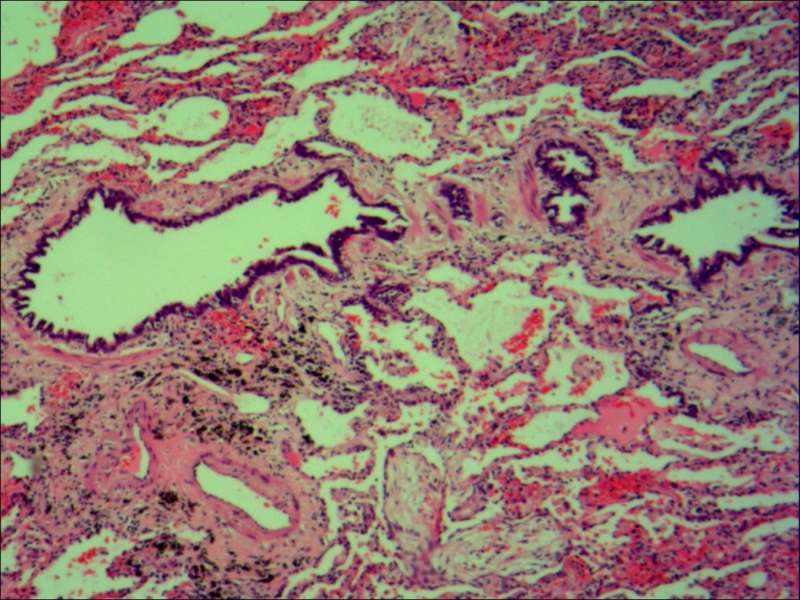

第二例隐球菌

整体是个类圆形,边界模糊(有晕征的感觉),肉芽肿一般都这样 里面也能见到许多小白球,大小从3微米到20微米不等 红细胞直径5-6微米 普通小淋巴细胞直径5微米 这里淋巴细胞挺多 有许多淋巴细胞,成堆

多核巨噬细胞吞了许多隐球菌 经常是反包围的感觉

这三幅是周围区,也有巨噬细胞,单核的多 都在肺泡腔内 所以有ggo样密度 过一段时间,晕就消失,有时是消退,有时是实性区扩大,盖住磨玻璃晕 那也是吞噬的作用,常代表免疫力正常 就是警察多了把肺泡填了

第二例也是类圆形结节状